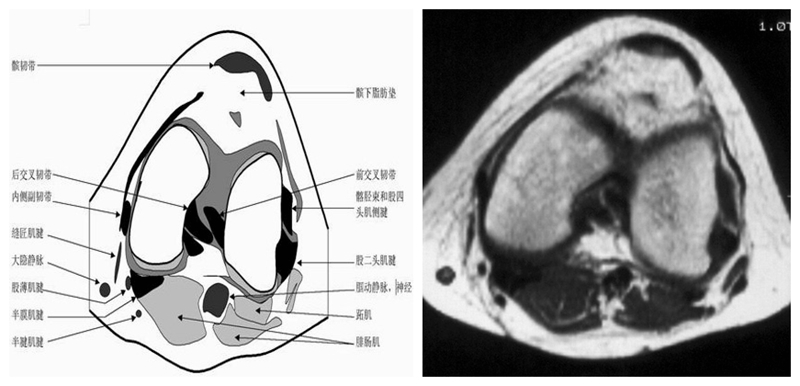

膝关节横断面MRI解剖

三维影像首选的方位,便于与CT比较,可准确地展现髌骨内外侧关节面。

横断面解剖第四层